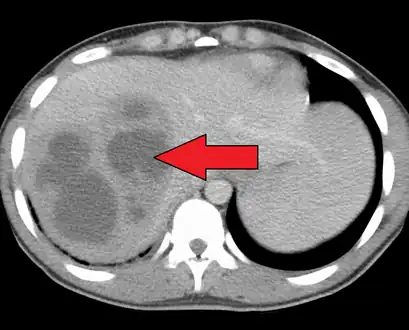

| Liver abscess on axial CT image: a hypodense lesion in the liver with peripherally enhancement. | |